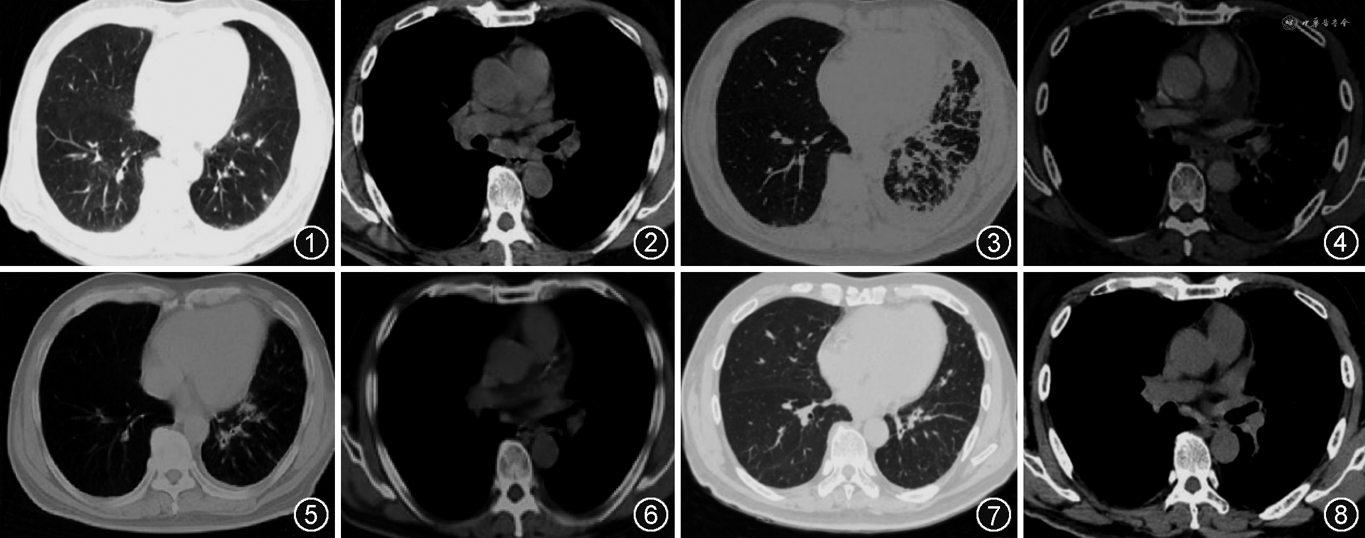

患者男,66岁,主因“反复咳嗽18个月”于2020年11月1日入院。患者2019年5月出现阵发性干咳,PET-CT(图1,2)提示左肺下叶前内基底段病灶,双侧肺门、纵隔、右侧锁骨上窝、肝门区、腹膜后多发淋巴结肿大。2019年9月外院胸膜病理提示多灶性肉芽肿性病变,可见中央坏死,周围可见上皮细胞及多核巨细胞,2次抗酸(+),六胺银(-),倾向结核;纵隔淋巴结病理为肉芽肿性炎,倾向结核。诊断为肺结核合并淋巴结结核,给予利福平(0.45 g,1次/d)、异烟肼(0.3 g,1次/d)、吡嗪酰胺(1.5 g,1次/d)、乙胺丁醇(0.75 g,1次/d)规律治疗9个月后,患者症状无改善,复查胸部增强CT(图3,4)可见左肺多发结节、斑片状密度增高影,左侧少量胸腔积液,双肺门、纵隔淋巴结增大并融合。2020年6月气管镜肺活检组织病原体宏基因组高通量测序(metagenomics next-generation sequencing,mNGS)提示结核分枝杆菌复合群(序列数19),奥布分枝杆菌(序列数302),星形诺卡菌(序列数64),病理未见明确肉芽肿病变及肿瘤。结合肺组织mNGS找到诺卡菌,外院考虑播散性诺卡菌感染可能,给予磺胺甲噁唑/甲氧苄啶(1.2 g,4次/d)、利奈唑胺(0.6 g,2次/d)治疗。2020年7月颈淋巴结培养提示马尔尼菲篮状菌(+),病理示淋巴结肉芽肿性炎。2020年10月复查胸部CT(图5,6)可见左肺及右肺下叶散在结节状高密度灶,左侧胸腔积液较前减少,双侧腋下、左肺门及纵隔淋巴结肿大较前略缩小。考虑患者肺部病变较前吸收,但淋巴结肿大较前改善不明显,于2020年11月1日再次收住我院呼吸与危重症医学科。

入院体检:体温36.3 ℃,脉率80 次/min,呼吸频率22 次/min,血压136/75 mmHg(1 mmHg=0.133 kPa),双侧颈部、右耳前、右耳下、枕后、右滑车、左耳后淋巴结肿大,心肺腹体检未见异常。实验室检查:白细胞计数14.55×109/L,血红蛋白浓度125.00 g/L,血小板计数347.00×109/L,中性粒细胞比值72.50%,淋巴细胞比值15.60%,中性粒细胞绝对值10.54×109/L,淋巴细胞绝对值 2.27×109/L。超敏C反应蛋白(hs-CRP)62.8 mg/L。痰涂片:较多G+球菌,少量G-球杆菌和G-杆菌。肺泡灌洗液X-pert、支气管刷片、气管镜取痰涂片及培养阴性。降钙素原(PCT)、1,3-β-D葡聚糖(G试验)、半乳甘露聚糖(GM)试验正常。纵隔淋巴结病理PCR:未见微生物。淋巴细胞亚群+绝对计数:CD3+T细胞54.11%(正常参考值:50%~84%),CD3+T细胞绝对计数 1 015.64个/μl(正常参考值:955~2 860个/μl),CD3+CD4+辅助/诱导性T细胞 31.65%(正常参考值:27%~51%),CD3+CD4+绝对计数593.94个/μl(正常参考值:550~1 440个/μl),CD3+CD8+抑制/细胞毒性T细胞 21.68%(正常参考值:15%~44%),CD3+CD8+绝对计数 406.85个/μl(正常参考值:320~1 250个/μl),CD3-CD19+总B细胞 2.61%(正常参考值:5%~18%),CD3-CD19+绝对计数 49.00个/μl(正常参考值:90~560个/μl),CD3-CD16+56+NK细胞42.64%(正常参考值:7%~40%),CD3-CD16+56+绝对计数800.33个/μl(正常参考值:150~1 100个/μl),CD4+/CD8+Th/Ts比值 1.46 %(正常参考值:0.68%~2.40%)。抗IFN-γ自身抗体滴度148 000 μg/L(吸光度值4,强阳性),STAT1-PI10为30.79。补体C4、免疫球蛋白A、免疫球蛋白G升高,补体C3、免疫球蛋白M正常。CA19-9、CA125、NSE、AFP、CEA正常,细胞角蛋白3.46 μg/L。彩超显示双侧颈部Ⅱ、Ⅲ、Ⅴ区及颈后、耳后下方可见肿大淋巴结,右侧最大约11 mm×6 mm,左侧最大约7 mm×6 mm。右颈淋巴结送至广州呼吸健康研究院会诊:淋巴结肉芽肿性炎症,符合马尔尼菲篮状菌感染。最终诊断:抗IFN-γ自身抗体免疫缺陷综合征、播散性马尔尼菲篮状菌病、诺卡菌感染、非结核分枝杆菌定植可能。给予伏立康唑(0.2 g,2次/d)治疗2个月后患者咳嗽消失,双侧颈部、右耳前、右耳下、枕后、右滑车、左耳后淋巴结及肘部肿大淋巴结消失。2021年1月患者复查胸部CT(图7,8)可见双肺散在斑点状、斑片状、条片状高密度影,肺门、纵隔多发淋巴结,双侧腋窝淋巴结,右侧为著,最大约33 mm×22 mm。患者右侧腋窝淋巴结明显疼痛,白细胞计数21.39×109/L,hs-CRP为147.83 mg/L,抗IFN-γ自身抗体强阳性(滴度117 594.1 μg/L,吸光度值3.8),考虑仍存在诺卡菌感染可能。给予伏立康唑(200 mg,2次/d)联合利奈唑胺(600 mg,2次/d)治疗2个月余,患者右侧腋窝淋巴结较前明显缩小。期间数次尝试停用利奈唑胺,但停药时间不超过3 d,淋巴结即明显肿痛,再次服用利奈唑胺后疼痛即明显缓解。复查抗IFN-γ自身抗体仍为强阳性(滴度121 921 μg/L,吸光度值4.1),STAT1-PI10为5.99。2021年6月和2021年11月分别给予利妥昔单抗600 mg治疗,复查抗IFN-γ自身抗体滴度较前下降(滴度88 305 μg/L,吸光度值2.8),STAT1-PI10为6.11,停用利奈唑胺及伏立康唑至今,患者无明显不适。